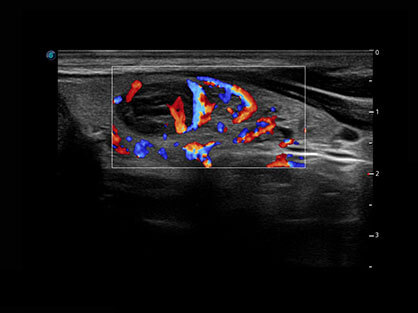

通过对组织运动信息、血流信号及背景噪声进行准确智能的阈值判定,高效提取出微弱血流信号,获得高灵敏度和空间分辨率的血流图像,为临床提供更加真实和丰富的诊断信息。

结合球速体育入口超宽频带探头技术优势,能够更好地获得高分辨力与高穿透力的平衡,保证图像质量,为临床诊断保驾护航。